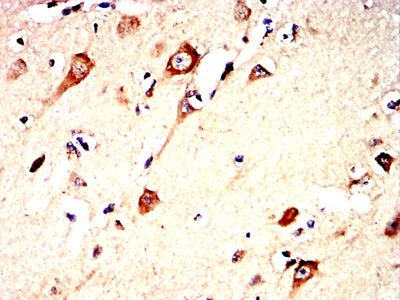

分类: 科研抗体货号: 32332别名: SCDO1应用: IHC,FCM反应种属: Human